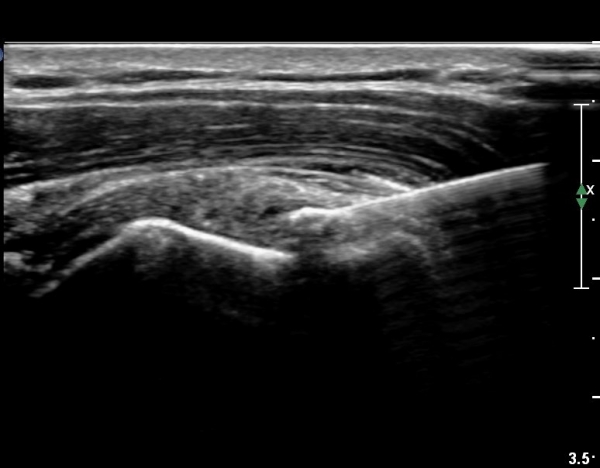

°ß°©ÇÏ±Ù°Ç È¾´Ü¸é°Ë»ç»ó ¼Ò°áÀý ÇÊÁú°ñº¯È­¿Í °ß°©ÇÏ±Ù°Ç Áߺο¡ °í¿¡ÄÚ µ¢¾î¸®°¡ °üÂûµÇ°í

¼®È¸ À§ÂÊ(¸Ó¸®ÂÊ)ÀÇ ÈûÁÙÀÇ Àú¿¡ÄÚ º¯È­°¡ °üÂûµÈ´Ù(»çÁø 4, 5).